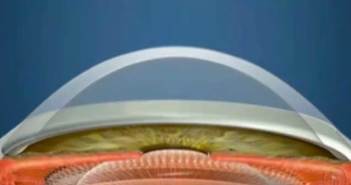

Οι μαλακοί φακοί επαφής είναι κατασκευασμένοι από έναν συνδυασμό υδρόφιλων πολυμερών που κάνουν κατακράτηση νερού…